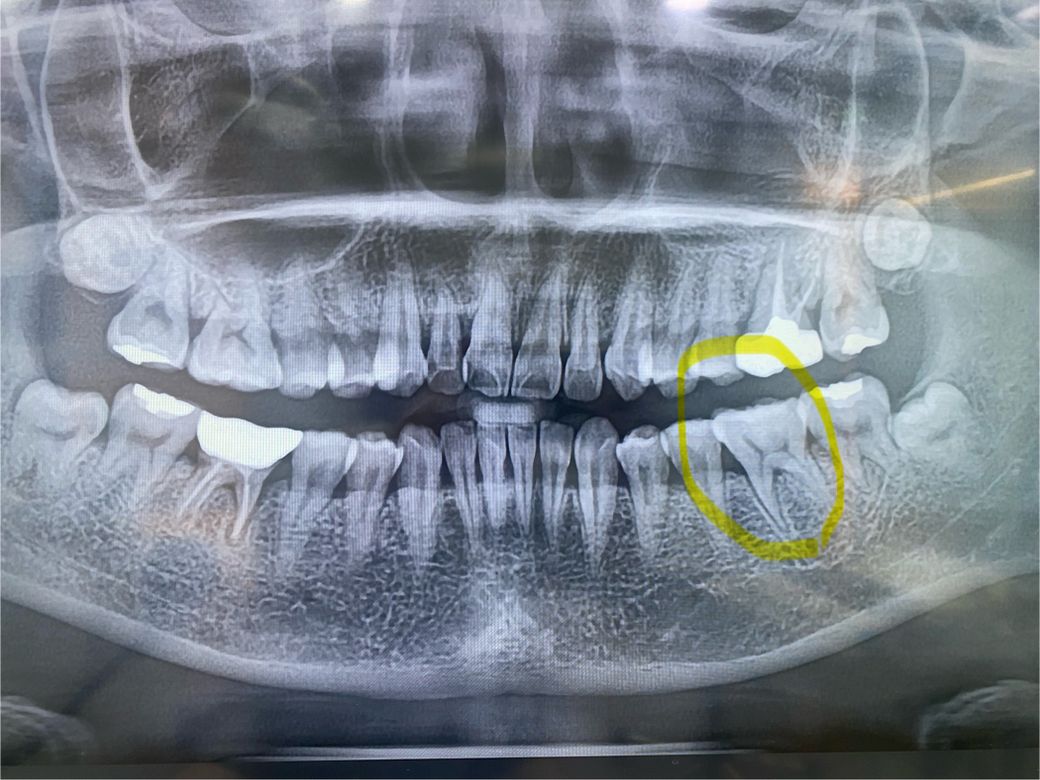

충치상태는 이랬습니다

-엑스레이